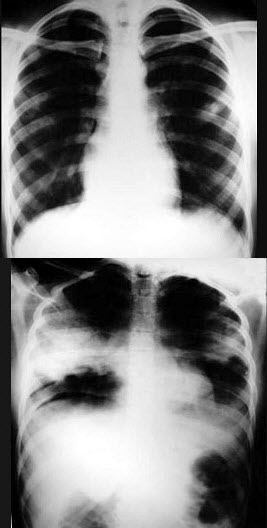

198、单项选择题

女,3岁,身体发育异常,如图所示,最可能的诊断为()

A.成骨不全

B.粘多糖病

C.软骨发育不全

D.佝偻病

E.侏儒症

254、单项选择题

男,70岁,胸痛,不咳嗽、发热,X线检查如图,最可能的诊断是()

A.左肺结核瘤

B.左侧叶间积液

C.左肺癌

D.左肺炎性假瘤

E.左肺错构瘤

297、单项选择题

男,23岁,胸闷伴胸痛1月余,胸片如图,最可能的诊断为()

A.右膈膨升

B.右下肺盘状不张

C.正常胸片

D.右侧肺底积液

E.右侧膈下脓肿